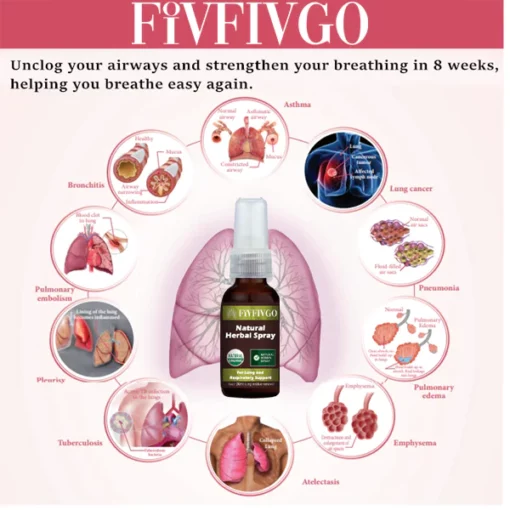

Fivfivgo™ Natural Herbal Spray

Price range: $17.01 through $78.76

Are you having trouble breathing due to allergies, asthma, smoking, COPD, pneumonia, bronchitis, or a weakened respiratory system? Fivfivgo™ Natural Herbal Spray for Lung and Respiratory Support gives you powerful lung support. Our formula is designed to cleanse your lungs and airways, channeling old mucus and lung buildup out. Unclog your airways and strengthen your breathing in 8 weeks, helping you breathe easy again. Relieve the symptoms and sequelae of lung cough caused by the COVID-19 virus.

Fivfivgo™ Natural Herbal Spray for Lung and Respiratory Support: The ingredients act on the lungs and respiratory system through the blood, stimulate and thin the mucus in the trachea and lungs, and help expel phlegm and lung residues within 2 hours, dredging the airway. It can also help correct your immune system, reduce allergic reactions through desensitization therapy, and effectively treat diseases such as respiratory allergies and asthma. The fifth-generation human-modified protein repair factor created by the Fivfivgo™ research team, combined with the extracts of mullein and Dendrobium officinale, helps the regeneration of lung trachea and alveolar tissue, giving you a healthy and unobstructed lung.